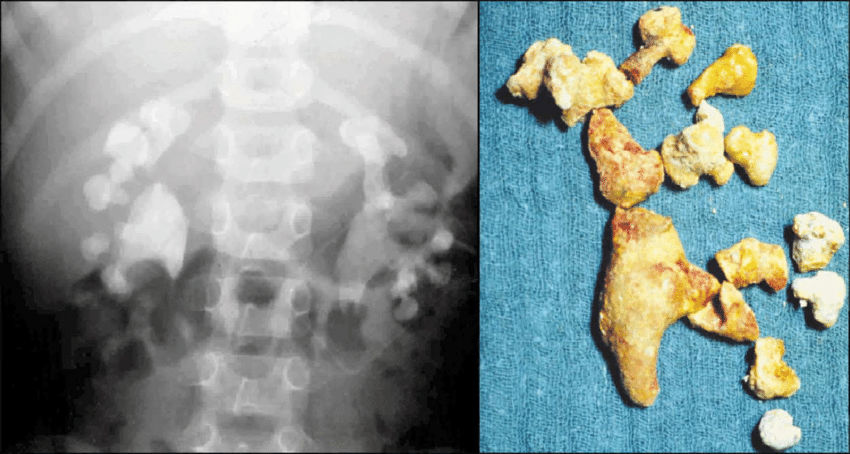

Kidney stones are hard deposits made of minerals and salts that form in your kidneys. They come from a mix of factors, leading to different types. Knowing how they form, their size, and what they’re made of is key. This knowledge helps us understand why they can be so painful when they move through your urinary tract.

Types of Kidney Stones

Kidney stones come in four main types. Knowing about them can help you prevent them. This is important for your health.

Calcium Oxalate Stones are the most common. They form when calcium and oxalate mix. Foods high in oxalate can increase your risk.

Uric Acid Stones happen when there’s too much uric acid in your urine. Eating too much protein can lead to this. So, watch your protein intake.

Struvite Stones are caused by urinary tract infections. Bacteria make ammonium, which leads to stone growth. Preventing infections can help avoid these stones.

Cystine Stones are rare and genetic. They happen when the kidneys release too much cystine. People with this condition need special diets and lots of water.